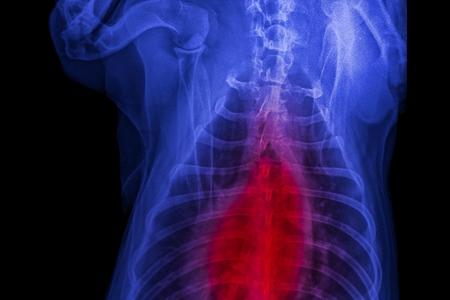

Cette infection respiratoire est assez fréquente chez nos chiens !

Comme chez l’homme, la pneumonie du chien est loin d’être une partie de plaisir. Cette affection provoque des toux et autres symptômes gênants. Comment la reconnaître ? Comment protéger votre animal de compagnie de cette maladie canine ? Explorons ensemble les différentes facettes de la pneumonie !